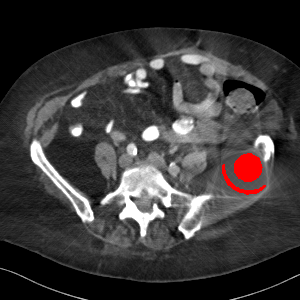

Visual comparison. As shown in Fig. 5, metallic implants such as spinal rods and hip prosthesis cause severe streaky artifacts and metal shadows, which obscure bone structures around them. cGan-CT cannot recover image intensity correctly for both cases. Sinogram domain or dual-domain methods perform much better than cGan-CT. LI, NMAR, and CNNMAR introduce strong secondary artifacts and distort the whole images. In NMAR images, there are fake bone structures around the metals, which is related to segmentation error in the prior image from strong metal artifacts. The segmentation error is also visible in NMAR sinogram. CNNMAR cannot restore the correct bone structures between rods in case 1. The tissues around the metals are over-smoothed in DuDoNet because LI sinogram and image are used as inputs, and the missing information cannot be inferred later. Our model retains more structural information than DuDoNet and generates anatomically more faithful artifact-reduced images.

Visual comparison. Fig. 7 shows two clinical CT images with metal artifacts. Case 1 is with moderate metal artifacts. cGan-CT does not suppress the artifacts completely and generates some fake details. LI, NMAR, CNN-MAR remove all the artifacts but introduce new streak artifacts, which is caused by the discontinuity in the corrected sinogram. DuDoNet outputs over-smoothed sinogram, which leads to blurred tissues close to the metal implants, such as muscle and bone. Only our model can provide realistic enhanced sinogram and remove the artifacts while retaining the structure of nearby tissues. Case 2 is very challenging as the rods bring strong metal shadows and bright artifacts around the vertebra. cGan-CT recovers the shape of vertebra but changes the overall image intensity. Other sinogram inpainting methods fail as the soft tissue and bone near the rods are heavily distorted. Our model removes part of the dark bands and reproduces correct anatomical structures around the rods.